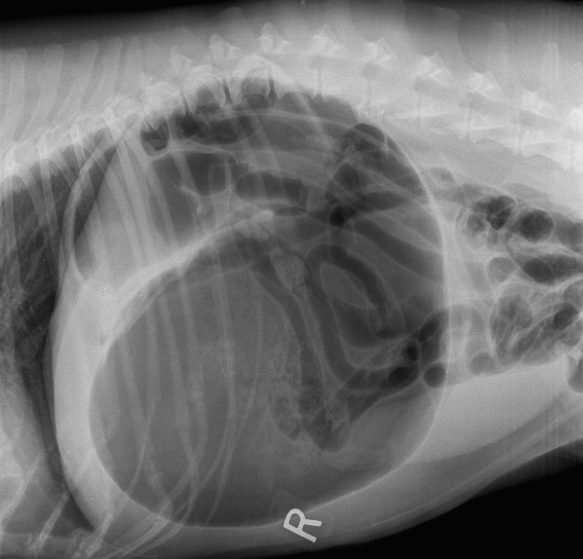

GDV classique